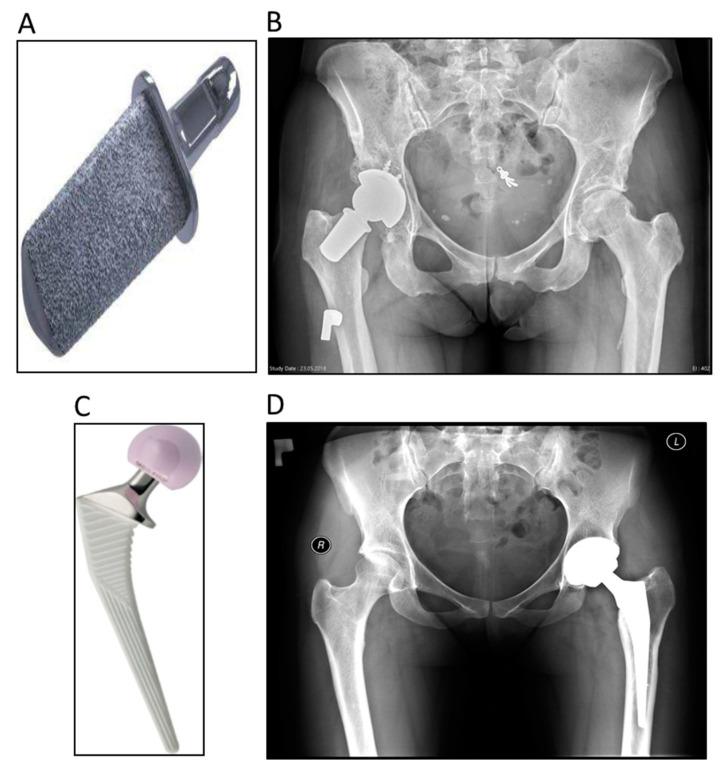

在初次全髋关节置换术中,短柄股骨颈与常规柄的短期功能结果相同。

Short-Term Functional Outcomes of Short Femoral Neck Stems Are the Same as Those of Conventional Stems in Primary Total Hip Arthroplasty.

(1) Background: In this study, two types of implants were compared-a conventional hip stem and a femoral neck prosthesis. (2) Methods: The femoral neck prosthesis study group included 21 patients, while the conventional hip stem control group was 40 patients. The first examination was the pre-op check, while the next ones were performed 6 weeks, 1 year, and 3 years after surgery. The Harris Hip Score (HHS), Western Ontario and McMaster Universities Osteoarthritis Index (WOMAC), Oxford Hip Score (OHS), University of California at Los Angeles Activity Score (UCLA), and Visual Analog Scale EQ (VAS EQ) forms were completed at each clinical study visit. (3) Results: The HHS in the femoral neck prosthesis group and the conventional hip stem group 6 weeks after surgery was 68.8 ± 16.47 and 67.6 ± 8.92, respectively, and 1 year after surgery, this was 93 ± 5.58 vs. 90.6 ± 5.17, respectively. The OHS of the femoral neck prosthesis group was 34.8 points after 6 weeks, 45.5 points after 1 year, and 43.9 points after 3 years. The respective values in the conventional hip stem group were 35.5, 41.55, and 42.13 points. The WOMAC values for the femoral neck prosthesis group were 70.6, 92.7, and 86 points, respectively, while for the conventional hip stem group, they were 74, 88.1, and 86.1 points. The UCLA scores recorded in the conventional hip stem group ranged from 3.15 to 5.05 points, but a higher mean value of 5.33 points was obtained in the femoral neck prosthesis group. VAS EQ was equal to 84 points three years after the operation. (4) Conclusions: The study showed no significant differences in the functional scores of both groups, and the new type of cervical femoral stem could be the first choice in younger patients.

(1)背景:本研究比较了两种植入物-传统髋骨柄和股骨颈假体。(2)方法:股骨颈假体研究组包括 21 例患者,而传统髋骨柄对照组为 40 例患者。第一次检查是术前检查,然后在手术后 6 周、1 年和 3 年进行后续检查。在每次临床研究访问时,都完成了 Harris Hip 评分(HHS)、安大略西部和麦克马斯特大学骨关节炎指数(WOMAC)、牛津髋评分(OHS)、加利福尼亚大学洛杉矶活动评分(UCLA)和视觉模拟量表 EQ(VAS EQ)表。(3)结果:手术后 6 周时,股骨颈假体组和传统髋骨柄组的 HHS 分别为 68.8±16.47 和 67.6±8.92,术后 1 年分别为 93±5.58 比 90.6±5.17。股骨颈假体组术后 6 周时的 OHS 为 34.8 分,1 年后为 45.5 分,3 年后为 43.9 分。传统髋骨柄组的相应值分别为 35.5、41.55 和 42.13。股骨颈假体组的 WOMAC 值分别为 70.6、92.7 和 86,而传统髋骨柄组则为 74、88.1 和 86.1。传统髋骨柄组的 UCLA 评分范围为 3.15 至 5.05 分,但股骨颈假体组的平均值为 5.33 分更高。手术后 3 年 VAS EQ 为 84 分。(4)结论:研究表明两组的功能评分无显著差异,新型颈股骨柄可作为年轻患者的首选。